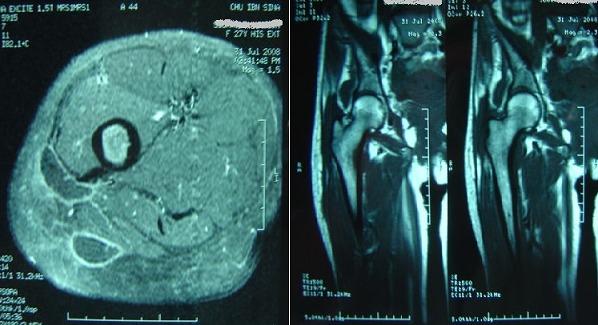

Trochanteric tuberculosis is a rare disease (<2% of osteoarticular tuberculosis), even in high-endemic countries. It is characterized by insidious symptoms. For this reason, diagnosis is often delayed. The authors report a series of 9 cases, the diagnosis was made by bacteriological and histological examinations after imaging assessment (ultrasound, MRI, CT scan). The treatment of this disease is medical (anti-tuberculous antibiotic). Surgical treatment is usually reserved for complications and improves disease progression.

转子结核是一种罕见疾病(在骨关节结核中占比不到2%),即便在高流行国家亦是如此。其症状隐匿,因此诊断往往延迟。作者报告了9例病例系列,通过影像学评估(超声、磁共振成像、计算机断层扫描)后经细菌学和组织学检查做出诊断。该疾病的治疗为药物治疗(抗结核抗生素)。手术治疗通常用于治疗并发症并改善疾病进展。